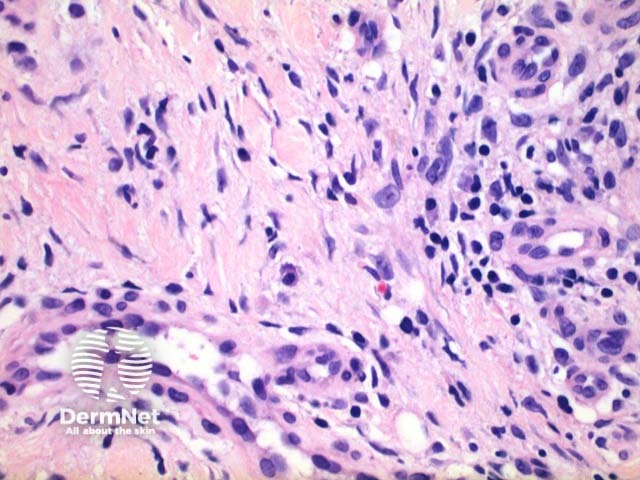

Scanning power view of necrobiosis lipoidica demonstrates a layered inflammatory process and alternating zones of necrobiosis involving the full thickness of the dermis (Figure 1). The changes tend to become more pronounced deeper in the dermis and may extend into the septal panniculus (Figures 2 and 3). The areas of necrobiosis are poorly defined and run into each other with broad foci of inflammatory infiltrate intervening (Figure 4). This may form a stacked ‘lasagne’ type appearance. A variable histiocytic infiltrate with multinucleated giant cells surrounds these areas. The accompanying inflammatory infiltrate is predominantly lymphocytic with plasma cells and occasional eosinophils (Figure 5). As lesions age an increasing degree of dermal fibrosis is seen.

Figure 4

Figure 5